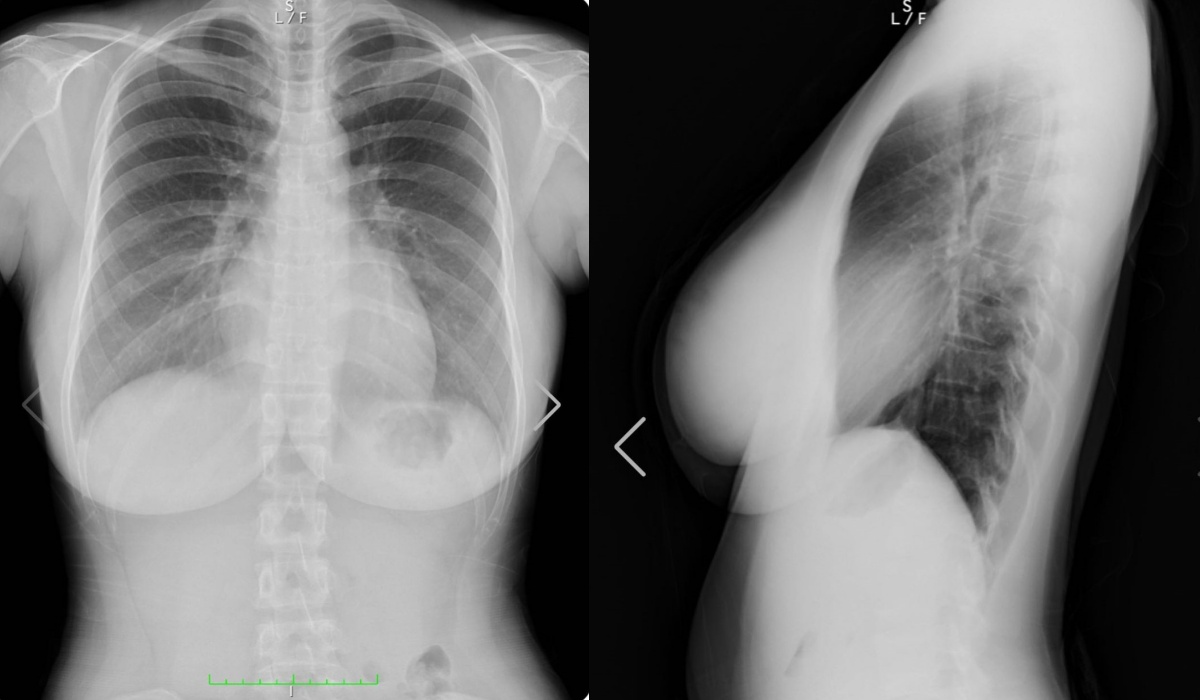

只見她上傳了一組「胸部 X 光片」,同時曬出正面、側面乳房,表示自己的體檢數值相較於前 2 年更健康了,從圖片中可以明顯看出,她的「I 杯豪乳」中並無填充物,傲人車頭燈完全是遺傳的。

此外,她也透露右胸處的黑色影子是胃泡,大家不用太擔心,並表示自己會持續透過運動來維持身體健康。由於天木純在去年 8 月時曾確診 COVID-19,經過一番休養後,如今公開自己健康的體檢結果,不僅讓粉絲放下心中大石,同時也徹底打臉了過去質疑她的人。